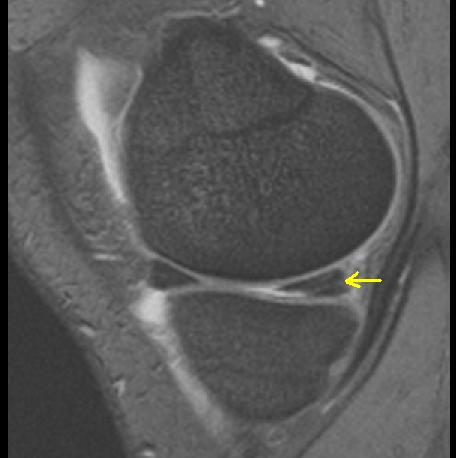

Riss im Innenmeniskus-Hinterhorn (siehe Pfeil, Ansicht von der Seite). Das Vorderhorn ist intakt